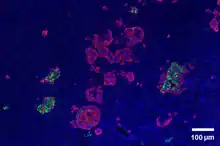

Through different microscopy techniques, the structural related details of PP cells have been able to be better understood. This is inclusive of how big they are, what their cellular membranes look like, the proteins associated with them, and even their size. PP cells are elongated cells. Another one of these details can be noted in insulins secretory granules, or container like buds, that store insulin within a cell. In PP cells, the size of the insulin granules are smaller and spherical and similar to those in alpha cells. This is noted in human PP cells, but different animals have been shown to have different sized granules compared to humans, like rodents. In cats and dogs, PP cells have large granules.[6] In rats, PP cells have few granules, similar to humans. In dogs, some PP cells are located in the walls of the antrum of the stomach.[3]